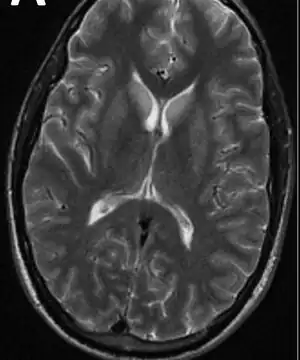

Neuroimaging and lumbar puncture (LP) are both essential methods of diagnosing viral encephalitis. Computed tomography (CT) or magnetic resonance imaging (MRI) help identify increased intracranial pressure and the risk of uncal herniation before performing an LP. Cerebrospinal fluid (CSF), if analyzed, should be analyzed for opening pressure, cell counts, glucose, protein, and IgG and IgM antibodies. CSF testing should also include polymerase chain reaction (PCR) testing for herpes simplex viruses 1 and 2 and enteroviruses. About 10% of patients have normal CSF results. Additional testing, such as serology for various arboviruses and HIV testing, may also be performed based on the individual's history and symptoms. Brain biopsy and body fluid specimen cultures and PCR may also be useful in some cases. Electroencephalography (EEG) is abnormal in more than 80% of viral encephalitis cases, including those who are experiencing seizures, and may need to be monitored continuously to identify non-convulsive status. Lack of testing resources may prevent accurate diagnosis.[1][5]

- For herpes simplex virus encephalitis, a CT scan may show low-density lesions in the temporal lobe. These lesions usually appear 3 to 5 days after the start of the infection.